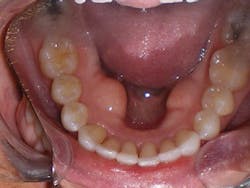

Sandra was excited to begin treatment. So her case was submitted, developed, and delivered in short order. Her treatment involved 24 aligners, which took exactly 12 months of treatment time.

Upon completion of treatment, she had a healthy, stable, and functional occlusion. Notice the clefting, recession, and abfraction improvements in the photographs related to her case. This validates my objection to the current standard of care of "waiting and watching" for conditions to worsen. Instead, my hygienists and I educate patients on the long-term solutions of clear aligner therapy so they can make educated choices regarding their oral health.